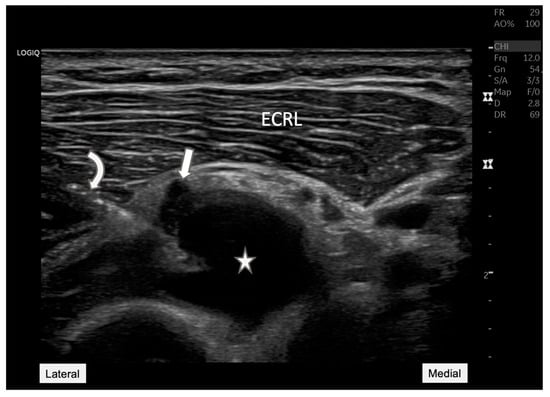

Figure 2. Radial nerve entrapment at the Arcade of Frohse. Longitudinal ultrasound view of the posterior interosseous nerve (arrow) depicting the nerve compression at the Arcade of Frohse (arrowhead). The nerve is visibly constricted by an underlying anechoic cyst (star). This image demonstrates the value of ultrasound in visualizing soft tissue structures, providing essential diagnostic insights into the mechanisms of neuropathic pain and potential therapeutic targets. ECRL: Extensor carpi radialis longus.